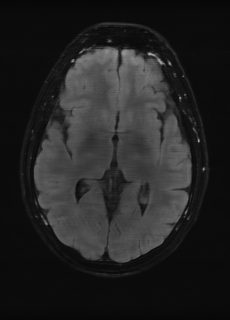

As we observe from the right image in Fig. 2, our BRM, both from MIMO and SISO settings, predicts the performance of dedicated models with a high correlation. We further choose the best three , and perform the last stage of fine-tuning accordingly to (6). A visual evaluation on real data is shown in Fig. 3. For simulated data, please refer to the Supplemental Material section.

Base on the best performing , we perceive that among , , and FLAIR, the results are best when is sampled the most. We suggest that this makes intuitive sense as images provide the best contrast out of the three sequences, which can compensate for the details lost in other images. The same observation can be made on the simulated data, where both and FLAIR show good contrast. When the time setting is changed to non-uniformity, we can see that our search for the best sampling strategy reflects the change. is sampled more as a result of faster acquisition time, while is still sufficiently sampled.

| Sequence | LR | SISO | MIMO | MIMO tuned | GT |

|---|---|---|---|---|---|

(a) 34.38/0.9371

(a) 34.38/0.9371

|

(b) 42.42/0.9883

(b) 42.42/0.9883

|

(c) 44.60/0.9920

(c) 44.60/0.9920

|

(d) 45.50/0.9940

(d) 45.50/0.9940

|

(e) PSNR/SSIM

(e) PSNR/SSIM

|

|

(f) 29.74/0.8903

(f) 29.74/0.8903

|

(g) 36.25/0.9734

(g) 36.25/0.9734

|

(h) 36.42/0.9752

(h) 36.42/0.9752

|

(i) 37.70/0.9832

(i) 37.70/0.9832

|

(j) PSNR/SSIM

(j) PSNR/SSIM

|

|

(k) 39.89/0.9311

(k) 39.89/0.9311

|

(l) 43.94/0.9864

(l) 43.94/0.9864

|

(m) 44.74/0.9883

(m) 44.74/0.9883

|

(n) 45.49/0.9894

(n) 45.49/0.9894

|

(o) PSNR/SSIM

(o) PSNR/SSIM

|